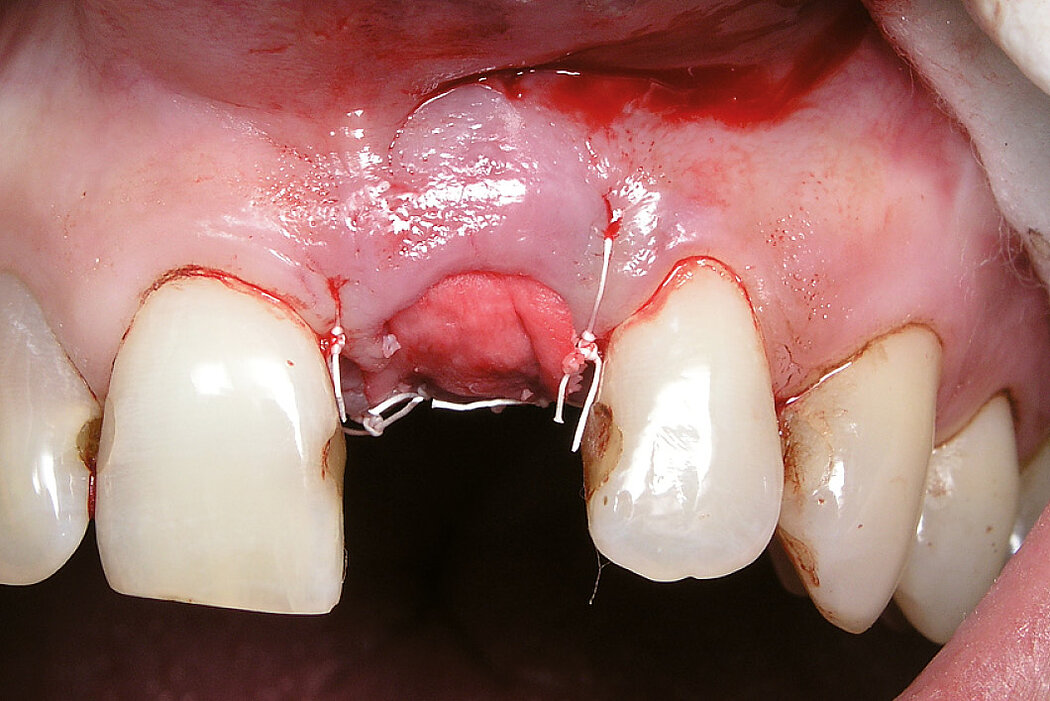

颊侧骨壁开窗的牙槽嵴保存(开放性愈合)

病例来自 Dr. Georg Taffet

德国,里拉辛根-沃布林根

临床挑战

Geistlich Bio-Oss® 和Geistlich Bio-Gide® 拥有20余年的使用经验,始终坚持“never change a winning team(永不改变成功策略)”的理念,对于复杂适应症同样如此。

目的/方法

替换牙根垂直断裂以及颊侧骨开窗的难以治愈的中切牙。前庭已经出现瘘管。

结论

牙槽嵴保存技术可有效减少骨量流失。

拔牙前与拔牙后7年的比较